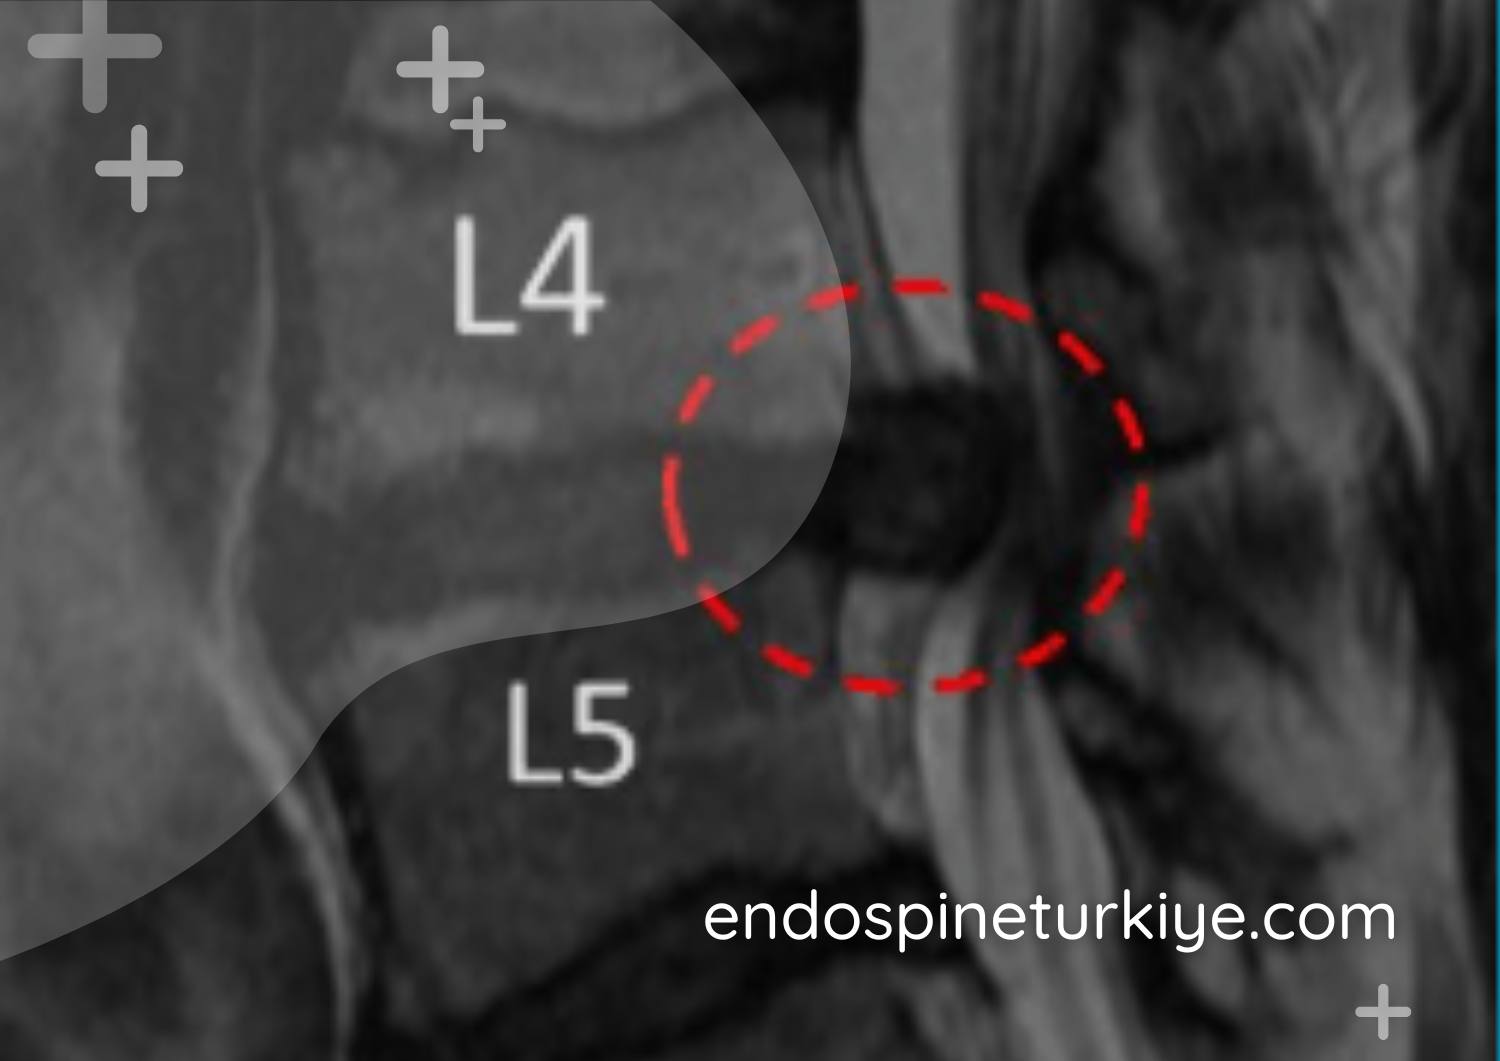

Dar kanal lomber MR görüntüsü - spinal stenoz teşhisi

Lomber MR görüntüsü - omurga kanalında daralma (spinal stenoz)